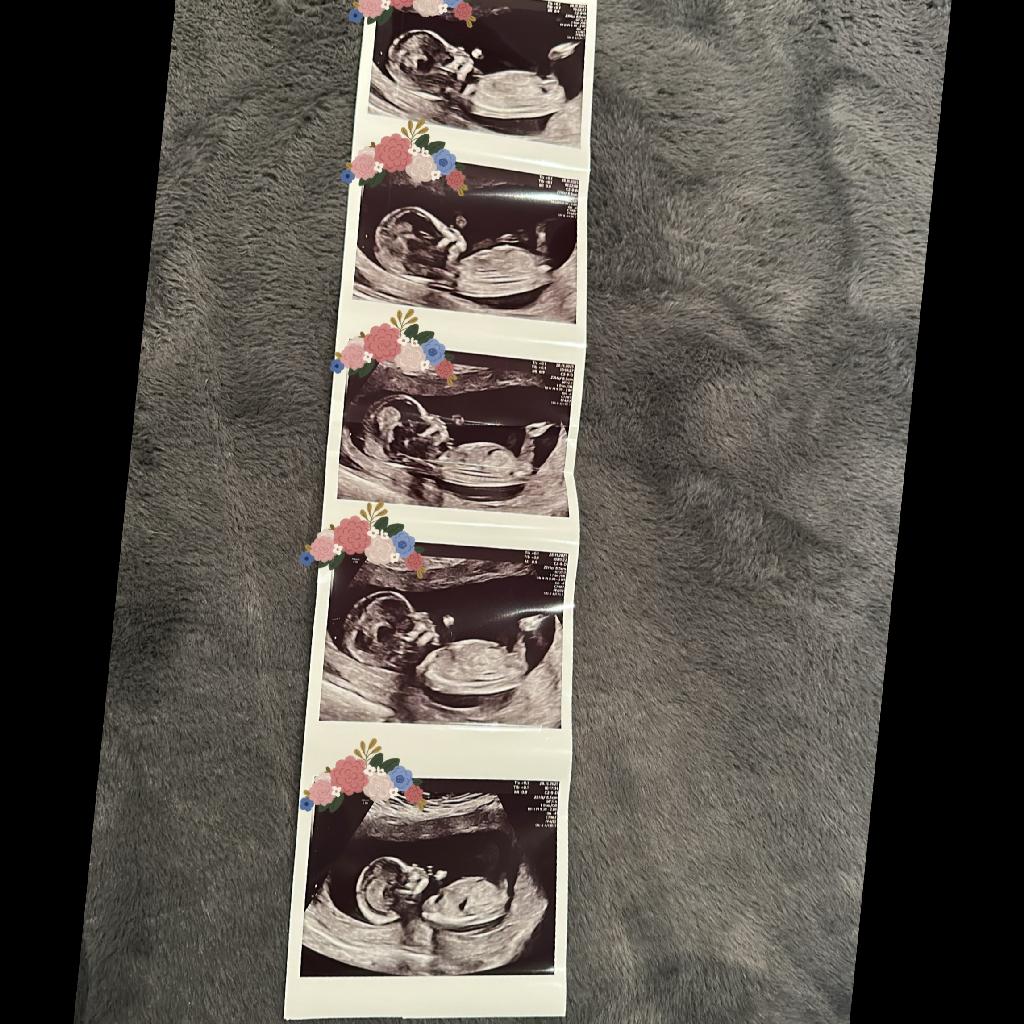

AnonymBruker Skrevet 2 timer siden #1 Skrevet 2 timer siden Hva synes dere om nub theory? Jeg har betalt for å gjette kjønn på nub theory metode og de sa 98% gutt. Viktigste er sikkert frisk baby men ønsker jente da jeg har 2 gutter fra før og vi tenker det siste barn 🥹Hva synes dere? Anonymkode: 94184...bc6

AnonymBruker Skrevet 2 timer siden #2 Skrevet 2 timer siden Hm noen bilder gutt noen jente. Best å vente ❤️ Anonymkode: 8656f...c6e

AnonymBruker Skrevet 2 timer siden #3 Skrevet 2 timer siden De mener de nederste bilde der kjønnet ses så ut som penis men er ikke det lårbein? Jeg må uansett vente er bare så spent. Anonymkode: 94184...bc6

AnonymBruker Skrevet 2 timer siden #4 Skrevet 2 timer siden AnonymBruker skrev (1 minutt siden): De mener de nederste bilde der kjønnet ses så ut som penis men er ikke det lårbein? Jeg må uansett vente er bare så spent. Anonymkode: 94184...bc6 Usikker. Om det er lårbeinet synes jeg det som ser ut som nub på de andre bildene er gutt. Anonymkode: 8656f...c6e

R2507 Skrevet 2 timer siden #5 Skrevet 2 timer siden AnonymBruker skrev (7 minutter siden): Hm noen bilder gutt noen jente. Best å vente ❤️ Anonymkode: 8656f...c6e De mener de nederste bilde der kjønnet ses så ut som penis men er ikke det lårbein? Jeg må uansett vente er bare så spent.